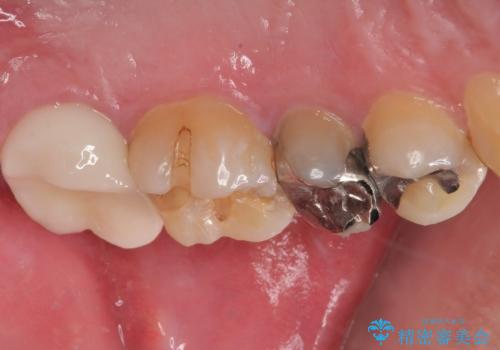

適合もよく、機能的に問題もなく、見た目も満足されていました。

正確な型どりにより再度虫歯になるリスクを低減してくれます。

今後はメンテナンスで通ってもらう予定です。